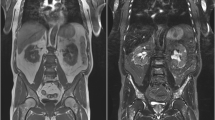

In MM, MRI may be normal or show different patterns of bone marrow involvement such as focal, diffuse (Fig. 4) or micronodular. Concurrent pathologic fractures that mimic a benign pattern may be present [28].

Diffuse bone marrow involvement in a 78-year-old male patient with Multiple Myeloma. Bone marrow diffusely appears hypointense on T1-weighted image (A), hyperintense on sagittal STIR (B) and axial DWI (C). ADC value is 900 × 10−6 mm2 s−1 on ADC map (D). Note also multiple vertebral fractures (arrows in A and B) and a vertebral hemangioma (arrowheads in A). The patient died 1 year later

In the past few years, the evaluation of the bone marrow with DWI and ADC maps has gained a central role [30]. DWI is a highly sensitive functional imaging technique that produces images where contrast between tissues is based on differences in the motion of water molecules at a cellular level, thus it enables evaluation of cell density [31]. In particular, the greater the cellularity of a tissue (such as tumor tissue), the smaller will be the movement of water molecules. This will translate into an increase of signal DWI sequences (compared to the surrounding background) and a reduction in ADC values that represents quantitative value of this movement. Therefore, ADC values are inversely proportional to cellularity: the more cells there are, the less water movements and thus lower ADC [32]. ADC values of normal bone marrow are less than 600 × 10−6 mm2 s−1, with even lower values in elderly patients, where fat marrow prevails and limits water movement [33]. On the other hand, MM bone marrow lesions show ADC values between 600–700 and 1400 × 10−6 mm2 s−1 (Figs. 5 and 6) whereas after treatment ADC values are higher than 1400 × 10−6 mm2 s−1 due to increased interstitial water induced by cell death and vascular congestion (Fig. 7) [34].